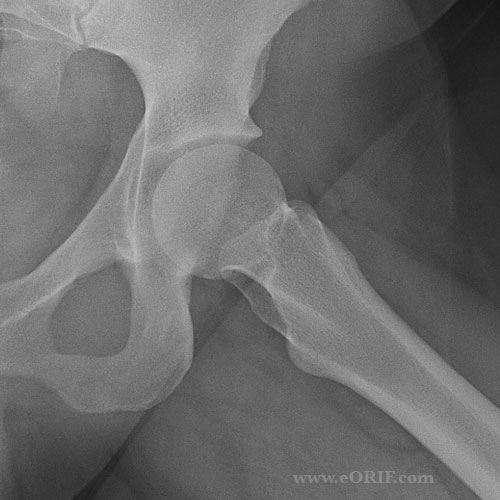

Hip Xray eORIF X Ray Hip Cross Table This view assesses the hip joint for any potential fractures, dislocations, bone lesions or degenerative diseases (i.e. The series is requested for a myriad of. The affected hip is internally rotated 15 degrees to profile the anterior femoral head/neck junction. To obtain a lateral view, cross. The hip series is comprised of an anteroposterior (ap) and lateral radiograph of the. X Ray Hip Cross Table.